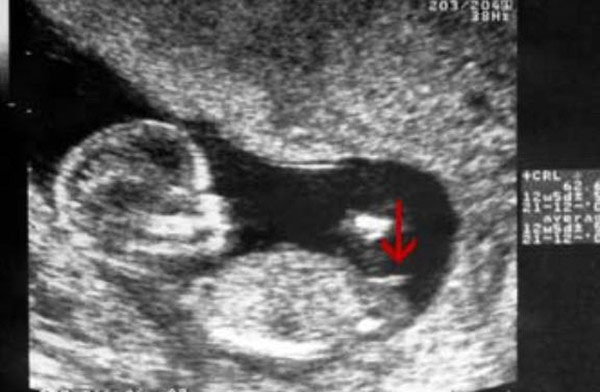

看nt图:网传,如果怀的是女孩的话在nt检查的时候nt图片中胎儿的身子一般都是平行的,看起来就是很平缓的躺在妈妈肚子里的,没有上翘以及脊柱线弯曲的弧度。都说nt图看怀男孩女孩很准,其依据就在这里,网传的是nt图平行生女孩,nt图弯着的生男孩。

已生女儿的宝妈透露称,nt图中胎儿的脊柱线和尾椎骨这里基本都是和身体保持平行的,脊柱线没有大于30度,尾椎骨这里也没有上翘。而男孩则刚好相反,脊柱线不仅要大于30度,甚至更多,而且尾椎骨这里还会上翘,据说这是因为男孩要发育生殖器的原因,而女孩则很平缓。